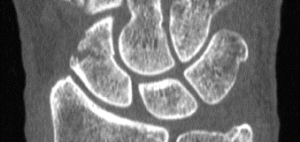

CT assessment of patients casted for a non-displaced scaphoid fracture shows union occurring at approximately 7.5 weeks, with a majority of fractures healing in less than 6 weeks, according to a 2016 study by Ruby Grewal et al. Similar studies using plain X-Ray demonstrated union time to be anywhere between 10 – 24 weeks. The authors noted the union time on CT may even be overestimated because the majority of patients’ first CT scan after casting was not until 6 weeks.

In a previous study, Professor Timothy Davis wrote CT studies demonstrate healing of a non-displaced fracture treated with a plaster cast can occur in as little as 4 weeks. If a fracture is displaced less than 2 mm, Davis said those CT studies suggest a plaster cast for 8 – 12 weeks.

CT is ideally performed for all scaphoid waist fractures in the first week after injury to classify whether they are displaced or non-displaced, said Professor Davis, an orthopedic surgeon at Woodthorpe Hospital in Nottingham, UK said in his research paper.

By using CT as a baseline, researchers at the Roth/McFarlane Hand and Upper Limb Center in London said they were able to identify fractures which may have appeared non-displaced on X-Ray, but were actually minimally displaced.

“We feel that the added visualization of CT over plain radiography enables the surgeon to properly select which fractures are appropriate for non-operative cast treatment with an expected high degree of union,” the researchers said in a study published in The Open Orthopaedics Journal.

Fifteen percent of acute fractures of the scaphoid waist fail to unite if treated non-operatively in plaster, resulting in a persistent loss of function, according to the 2013 article. Plain X-Rays do not clearly show fracture features such as displacement and communition. Previous inter-observer studies have shown radiographs of scaphoid fractures are neither sensitive nor specific.